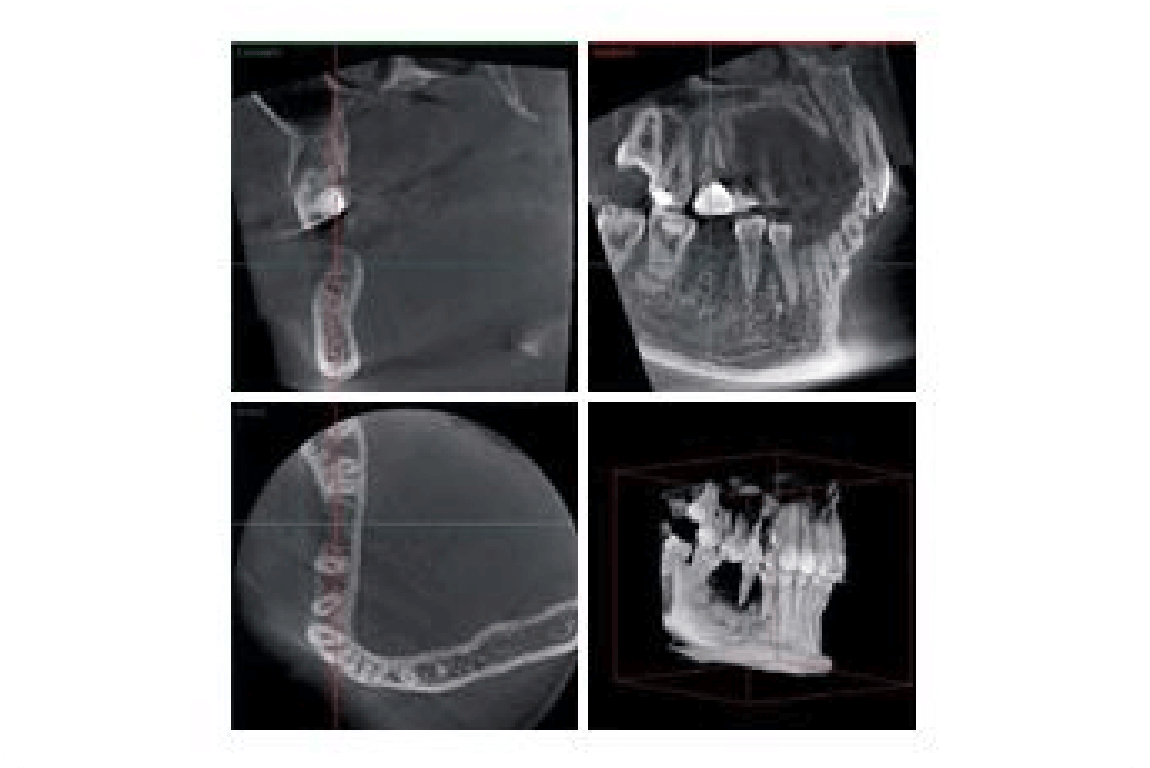

2次元のレントゲンでは把握しづらかったお口の中を立体的な3次元画像で確認できます。

口腔内の状態の縦・横・正面の3方向だけでなく、斜めからのスライス断面まで、さまざまな表現で表示することができるロメキシス3Dイメージングソフトウエアを搭載しています。画像再構成の精度も高く、実際の顎に限りなく近い立体画像を表示することができますので、より診断価値の高い3D画像を得られます。

従来のX線写真では平面での診断しかできませんでしたが、歯科用CTでは3次元の画像で3方向から確認でき、多くの情報が得られます。

顎の内部構造も、リアルに確認できます。 -